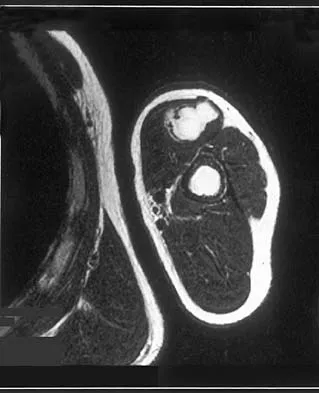

A 40-year-old woman has a symptomatic mass on the anterior aspect of the ankle. She reports no constitutional symptoms. An MRI scan is shown in Figure 12. What is the most likely diagnosis?